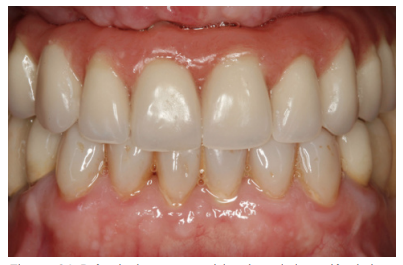

Cuatro meses después se procede a la carga de los implantes insertados en esta segunda fase quirúrgica. De nuevo se opta por unas segundas prótesis provisionales de carga progresiva, elaboradas del mismo modo que las anteriores Tres meses después la oclusión está preparada para la confección de la prótesis definitiva, por lo que se transforma la prótesis en una prótesis metal-cerámica, atornillada sobre transepitelial confeccionada mediante cad-cam (Figuras 25-26). La paciente ha recuperado la función demandada, así como la corrección de la oclusión de la prótesis completa, que presentaba una mordida cruzada lateral derecha con disminución de la dimensión vertical al inicio del tratamiento. La paciente acude a sus revisiones y el tratamiento se mantiene estable tal como se muestra en las imágenes tomadas a los 10 años de seguimiento (Figuras 27-28).